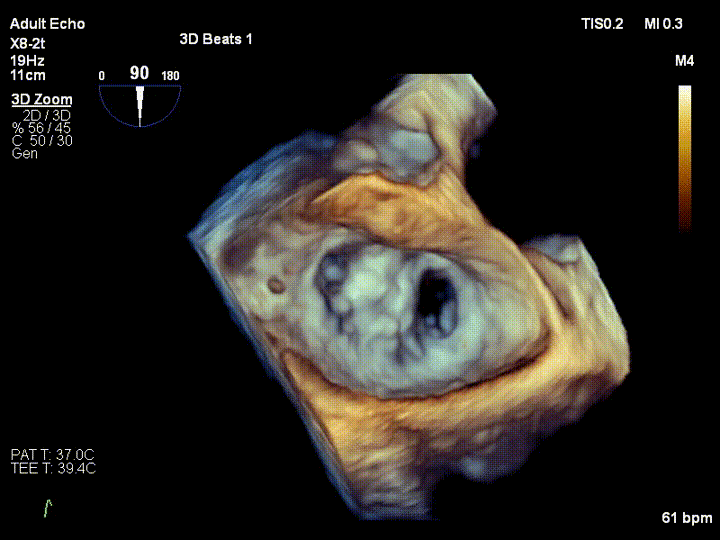

该患者是一名71岁老人,反复气喘3年余,加重3周余。入院诊断为二尖瓣后叶脱垂伴重度关闭不全,超声心动图提示:二尖瓣后叶脱垂伴重度关闭不全。该患者同时合并冠心病、房颤、外周动脉硬化、肾功能不全等疾病,心脏团队评估患者开胸手术风险极高,微创二尖瓣修复手术是最适合的治疗方式,因此患者及家属充分考虑后选择该项技术治疗,并签署本研究知情同意书,王焱教授团队全面评估后确认该患者符合本研究入选标准,注册入选成为福建省第一个入组治疗的患者。

王焱教授团队和美国弗吉尼亚大学医学中心David Scott Lim教授、香港亚心医院林逸贤教授术前详细评估并制定了相应的手术策略,并在手术当天在线指导。在浙江大学附属第二医院王建安书记结构团队核心成员刘先宝主任的现场指导下,王焱院长团队顺利完成股静脉穿刺,然后在食道超声指引下顺利穿刺理想位置的房间隔,肝素化后,放置25F鞘管至左房,测定左房压,随后顺利于二尖瓣前后叶植入两枚二尖瓣钳夹装置,术前患者二尖瓣重度反流即刻减轻至微量,左房压力即刻减低,预示着患者的临床症状将得到明显改善。手术全程用时不到2小时,患者术后即刻拔管苏醒。